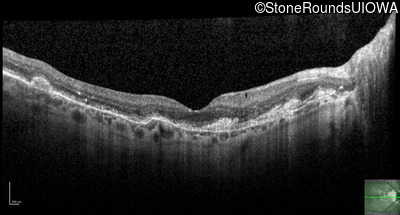

Optical Coherence Tomography - Right - 20/25 +1

Exemplar / OCT Stack